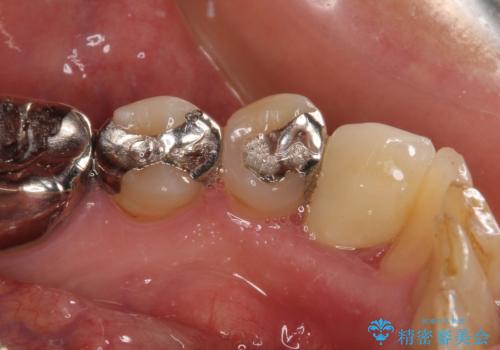

当該歯である犬歯は歯根が長く、安易に抜歯することはおすすめできないため、まずは部分矯正により歯根を引っ張り出し、その後歯周外科処置により歯槽骨や歯肉の状態を整え、最終的にはオールセラミッククラウンにて補綴治療を行うこととしました。

矯正治療中は汚れが溜まりやすく、歯肉からの出血が続きましたが、最終的には歯を保存して安定した状態で補綴治療を行うことができました。